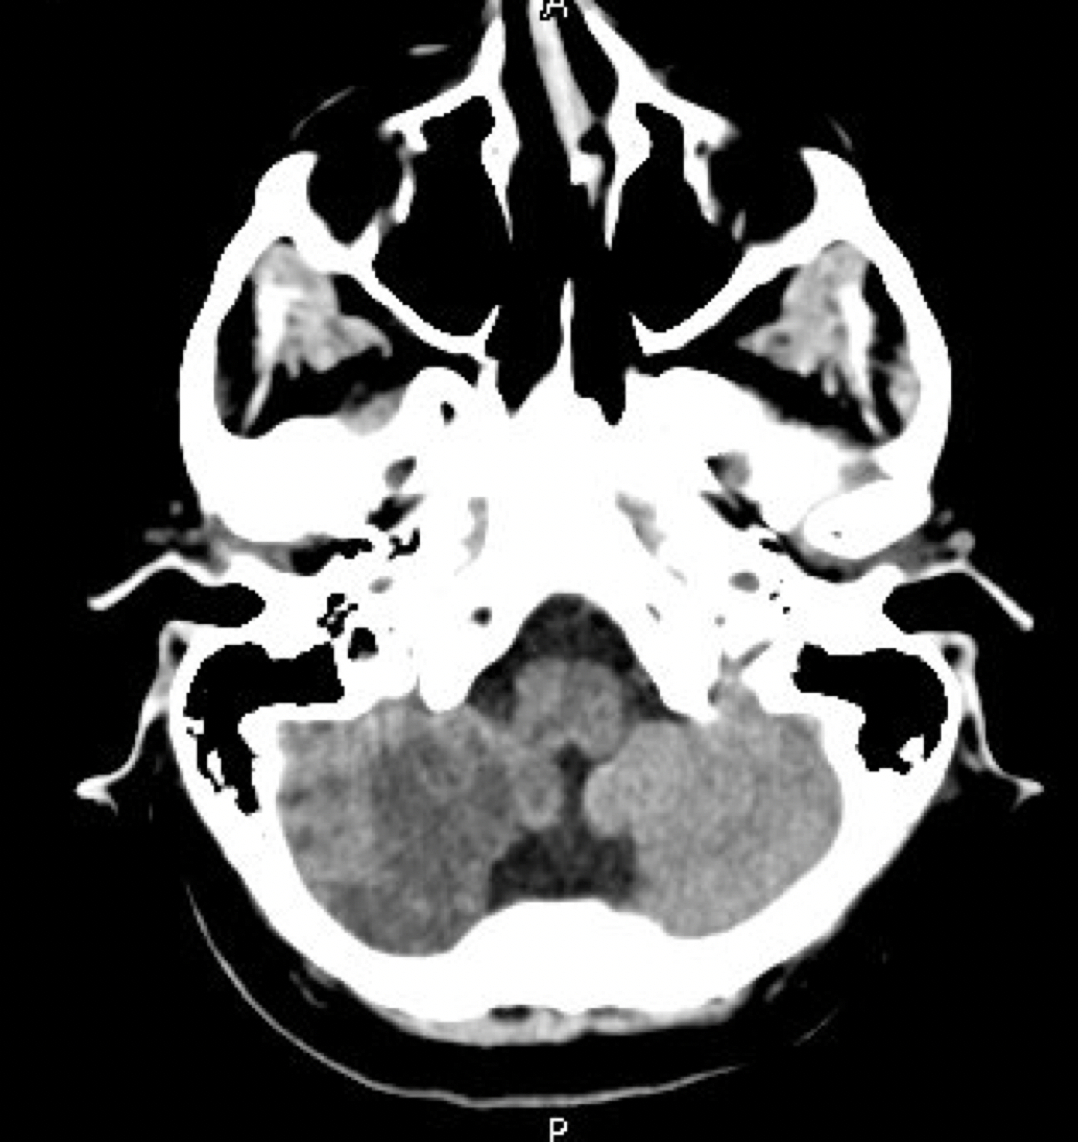

Our patient is a 71-year-old female with a history of hyperlipidemia who presented with vomiting. She reported an episode of chest pain 1 week prior that spontaneously resolved. Electrocardiogram showed anteroseptal Q waves and anterior ST segment elevations. Emergent catheterization was delayed due to concerns of nonviable myocardium with Q waves and the distant history of chest pain. Patient was tachycardic and tachypneic, but blood pressure was initially stable on arrival. Physical exam revealed elevated jugular venous pressure and mild crackles in the lung bases. Echocardiogram showed severely reduced ejection fraction of <15% with akinesis of the mid to apical walls. High sensitivity troponin increased to >60,000. Patient later developed tenuous blood pressure, increased oxygen requirement, and lactic acidosis. She was taken for a right and left heart catheterization and underwent successful aspiration thrombectomy with stenting of the proximal left anterior descending artery. MAFP was placed during the procedure and was removed on hospital day 7. After pump removal, the patient began complaining of new blurred vision and right-sided headache behind her eye. Bilateral miosis was noted without nystagmus. Initial computed tomography (CT) head reported no acute intracranial abnormalities. After two days of persistent symptoms, neurology was consulted and noted an acute infarct in the right cerebellar hemisphere after independent review of the CT head. Brain magnetic resonance imaging (MRI) showed subacute right posterior inferior cerebellar artery (PICA) territory infarct. The patient’s neurological symptoms gradually improved over her hospital course and she was discharged to a rehab facility.

MAFP can assist with coronary intervention and allow for myocardial recovery but comes with associated risks such as stroke. Cerebellar strokes can be rare with PICA being the most commonly involved artery. CT imaging may be normal in up to 25% of patients, which necessitates further investigation with MRI imaging. Early recognition of strokes during and after MAFP usage is essential to mitigate complications and improve future patient outcomes.